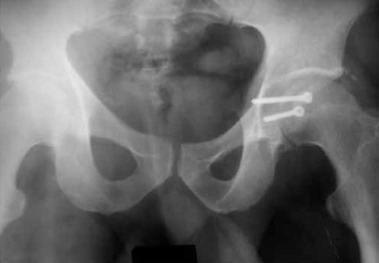

В случае отказа больного от аппарата внешней фиксации или при противопоказаниях производится скелетное вытяжение сроком 3-4 недели. Когда отломок проецируется на уровне или ниже ориентирной линии (рис. 4), разрез производится на 1 см ниже ее. Также тупо разводятся волокна большой ягодичной мышцы.

Рентгенография тазобедренного сустава до и после вправления. Перелом среднего отдела заднего края вертлужной впадины со смещением

Большая, средняя и малая ягодичные мышцы вместе с грушевидной отводятся кверху, верхняя близнецовая — книзу. Следует помнить о выходе из малого таза седалищного нерва под грушевидной мышцей в проксимальном ее участке. Также производится ревизия состояния хряща головки бедренной кости, отломка, установка его после промывания полости сустава, стабильная фиксация с элементами компрессии (рис. 5, 6).

Обзорная рентгенограмма таза. Состояние после открытой репозиции и фиксации среднего отдела заднего края вертлужной впадины 2 винтом. Стабилизация и разгрузка тазобедренного сустава в аппарате внешней фиксации

Рентгенография тазобедренного сустава в двух проекциях (прямая и аксиальная). Срок после оперативного лечения — 3 года